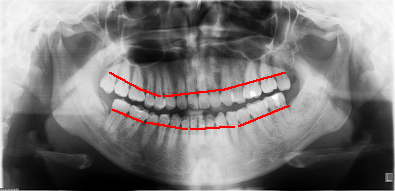

???

??

???????牙周相對(duì)健康患者牙槽骨的高度(紅線表示每個(gè)牙齒牙槽骨最高點(diǎn)的連線)

?

??????牙周病患者牙槽骨的高度(紅線同上,綠線則代表牙槽骨原來(lái)的水平高度)